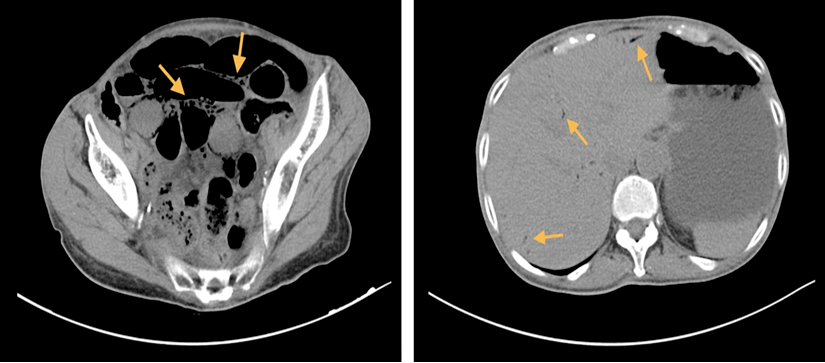

图2.可见扩张的肠腔内明显气液平,存在肠梗阻

腹部增强ct扫描显示十二指肠,空肠及邻近小肠可见多处气液平面.

腹部增强ct扫描显示胃显著扩张,多发小肠袢扩张伴气液平,回肠壁积气